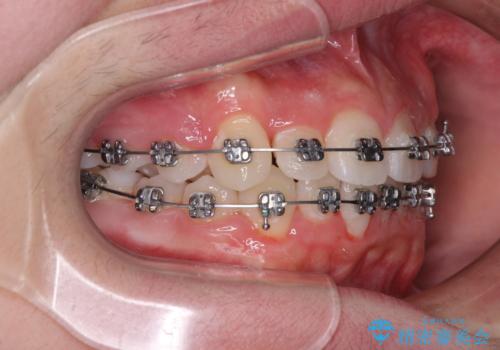

中学生のワイヤー矯正 クロスバイトを短期間で改善

- メタルブラケット

- 治療期間

- 11ヶ月

中学生であることから、治療期間を短縮できると判断し、ワイヤー矯正にて短期間で治療を行うこととしました。

叢生のため磨き残しの多い歯列でしたが、1年弱で治療を終了でき、磨き残しや歯肉の腫れが著しく改善されました。